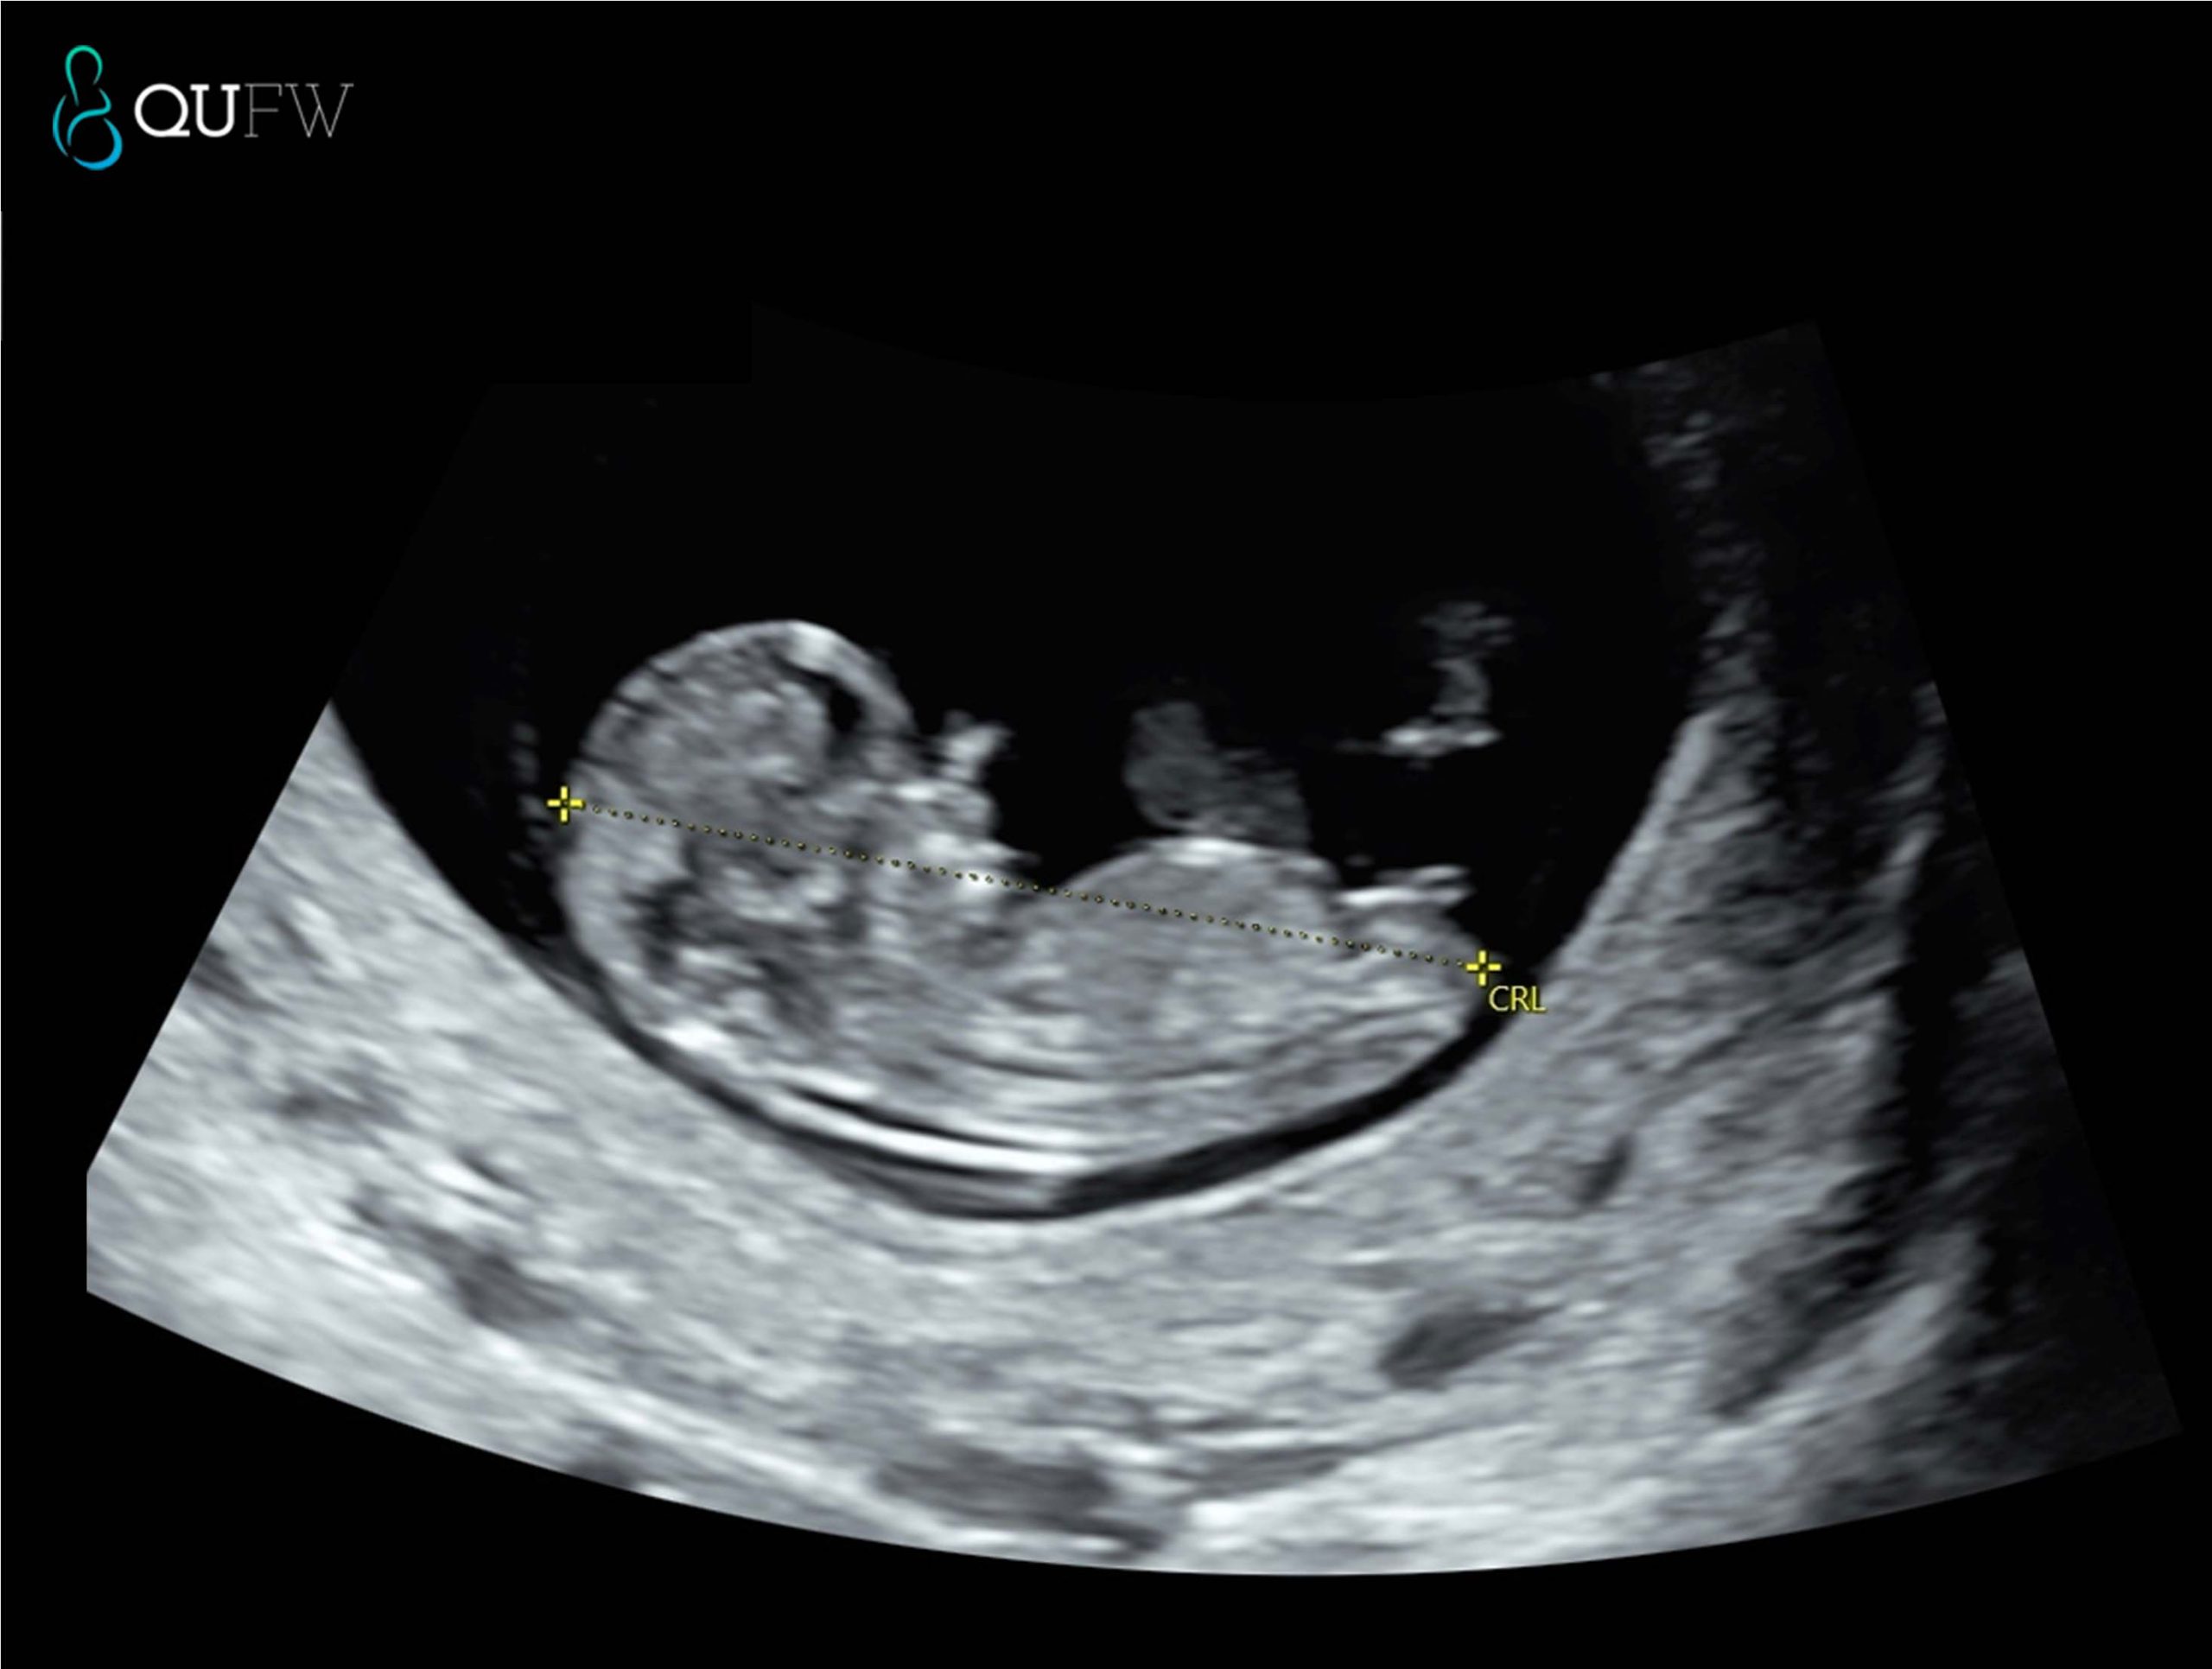

A viability scan confirms that the pregnancy is in the uterus, checks for a heartbeat, and assesses early development. A dating scan measures the crown–rump length (CRL) to estimate gestational age and your EDD. This timing offers a high degree of accuracy (± 5 days). You may be referred for a viability scan if you:

Dating scan prior to NIPT